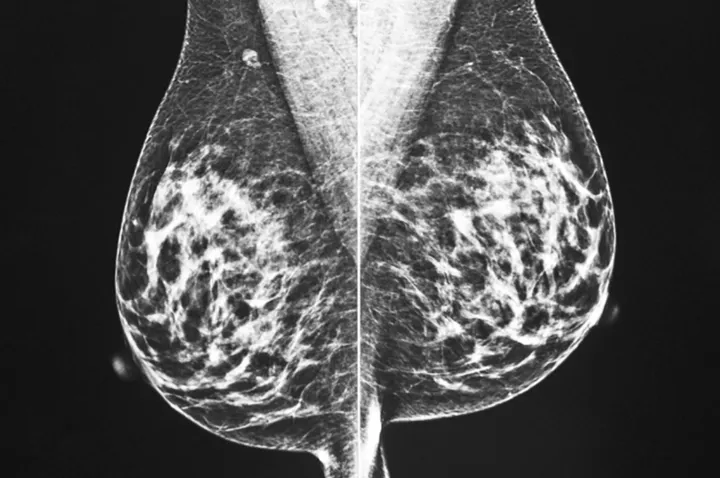

زندگی با سرطان از نگاه بسیاری ممکن است زندگی با مرگ باشد. اما مریم نجیب مردانلو نظر دیگری دارد. او مدتهاست با سرطان دست و پنجه نرم میکند و تجربیاتش را در کتابی تحت عنوان «سفر سرطانم؛ هرچه از زندگی مسالمتآمیز با سرطان آموختم» جمعآوری کرده است. این کتاب مدتی پیش بهصورت آنلاین منتشر شد.